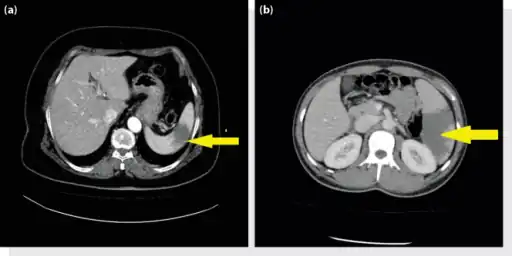

Healed splenic infarct

There is no specific treatment, except treating the underlying disorder and providing adequate pain relief. Surgical removal of the spleen (splenectomy) is only required if complications ensue; surgical removal predisposes to overwhelming post-splenectomy infections.[19]